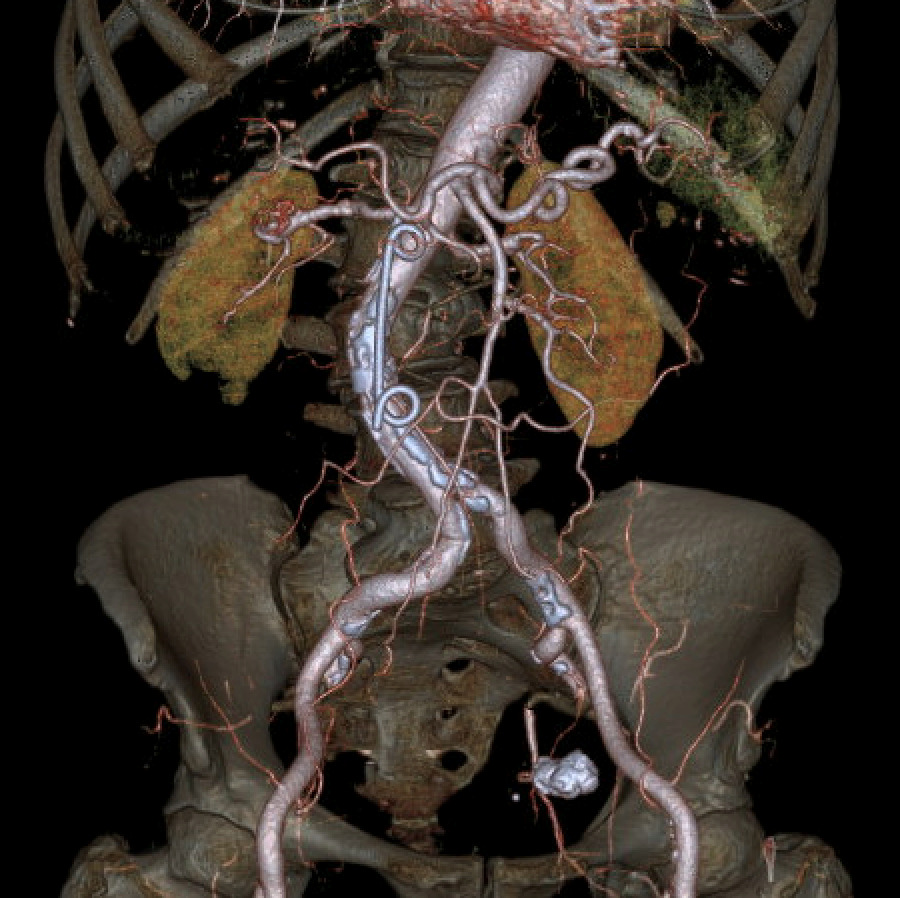

Despite biochemical improvement, the patient’s clinical course was complicated by persistent systemic inflammation and escalating abdominal pain. A contrast-enhanced computed tomography (CT) scan demonstrated features consistent with severe acute necrotizing pancreatitis, including extensive pancreatic oedema, areas of hypo-enhancement, marked peripancreatic fat stranding, and multiple peripancreatic fluid collections. The largest collection measured approximately 10 × 15 × 5 cm (Figure 1).